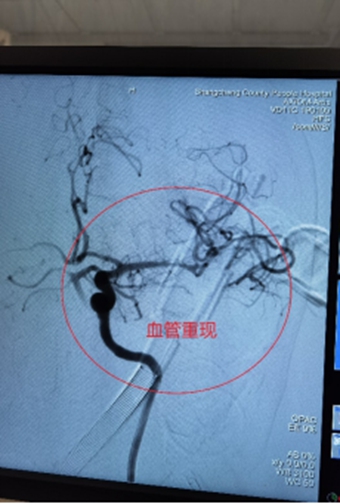

2、基底动脉栓塞,急诊导管抽栓+动脉溶栓1例;

0013.jpg

0014.jpg

0015.jpg

0016.jpg